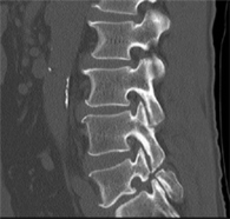

●腰椎椎間板ヘルニアと腰椎分離すべり症の手術を回避できました。

C・Nさん 49歳 男性

一年半前に自宅で重いものを持ち上げた際に、腰に激痛が走り、左足の痛みとシビレで歩けなくなりました。

整形外科では「腰椎椎間板ヘルニア」、「腰椎分離すべり症」と診断され、痛み止めと運動療法で痛みが治まっていました。

しかし、それから半年経ってまた、腰痛と左足の痛みとシビレが出てきて、神経根ブロック注射の後、2ヶ月くらい掛かって痛みが和らいでいきました。

ところがそれから更に1年経った今年になって、また同じ症状が現れ、整形外科を受診すると、腰椎椎間板ヘルニアが3か所あり、神経根ブロック注射をうけましたが、今回は効果がありませんでした。

「腰椎椎間板ヘルニア」と「腰椎分離すべり症」の手術を前提で通院治療している折に知人からなるほ堂仙骨調整を紹介され、「手術せず治ってくれれば」と、神頼みにも似た心境で施術を受け始めました。

腰椎椎間板ヘルニアと腰椎分離すべり症の手術を回避できましたなるほ堂仙骨調整を受ける前は、腰が痛くて寝床から起き上がるのがやっとで、歩くこともできませんでした。家から車でなるほ堂まで通う25分の間にも腰が痛くなってきていました。

週2回のサイクルで仙骨調整を受け始め、腰痛は楽になったりまた更に痛くなったりしながら10回目までは、それほど大きな変化は感じていませんでした。ちょうどその時期に、手術のための検査入院で、いままでブロック注射をしていない神経根部に注射をしましたが効果ないばかりか、余計に腰と足の痛みが増しました。更に、検査のため脊髄に造影剤を注射した後、頭が痛くなってしばらく動けない状態が続きました。そのような状態でも、医者はあまり気にしてくれなかったことや、ヘルニアの手術だけでは治らない可能性があるから、腰椎分離すべり症の手術で仙骨と腰椎をボルトで止めてしまうという手術内容や術後2から3カ月経たないと仕事に復帰できないという説明を聞いて、手術を受けることへの迷いが出てきました。

腰椎椎間板ヘルニアと腰椎分離すべり症の手術を回避できましたそうして、11回目の施術後から、腰と足の痛みが軽減してきました。なるほ堂仙骨調整で腰痛が軽減されていく可能性を感じ、気負いが無くなってきました。

それから1カ月経った今もよい状態が続いています。手術は中止しました。手術が成功しても10月頃と思っていた会社復帰の夢も施術を受け始めてから2カ月半で叶いました。

初回のときに「まずは、3カ月続けてみましょう。」という先生の説明が思い出されます。

ほとんど歩けなかったのが、今では30分は、足に違和感なしに歩けるまでに回復しています。さらなる改善を目指して、会社に通いながらも、週1回のなるほ堂仙骨調整を続けていこうと思っています。